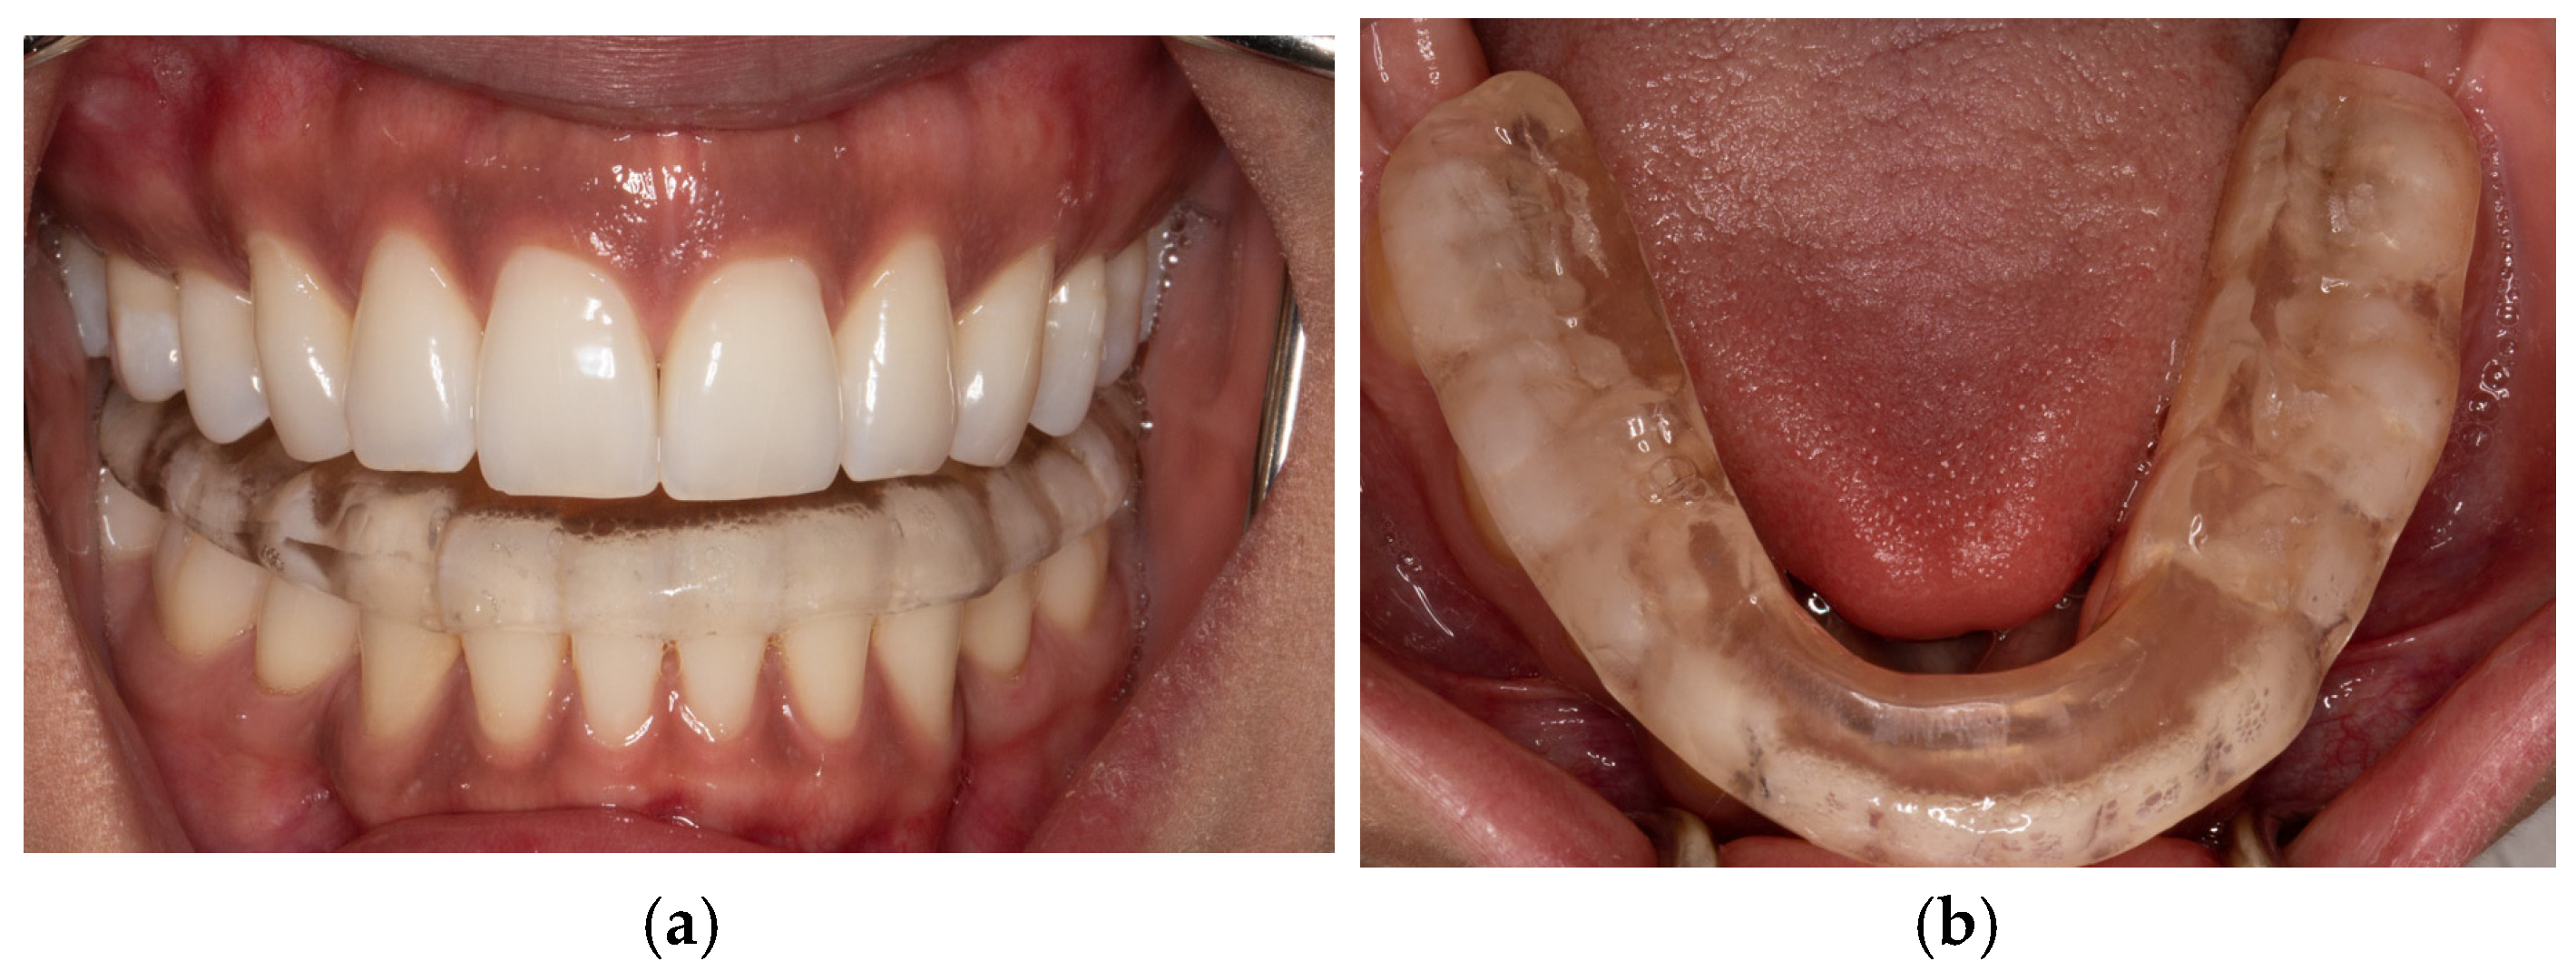

2.4. Controlled Mandibular Repositioning Method